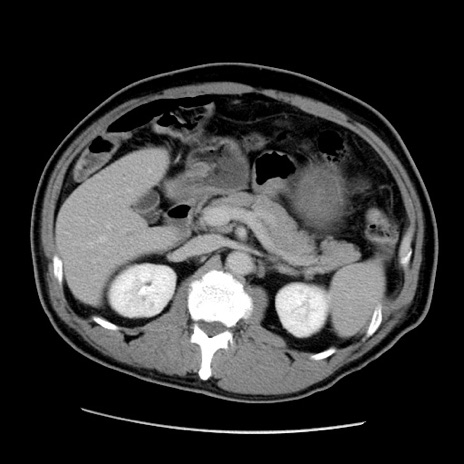

症例22(横断像)

【症例】50歳代男性

【主訴】腹痛

【現病歴】AVMからの被殻出血のため回復期リハ病棟入院中。 本日午後3時頃急に下腹部痛が出現した。

【既往歴】AVM、被殻出血、虫垂炎、高血圧

【身体所見】意識晴明、左半身不全麻痺、会話の理解は良好、36.5°C、腹部:膨隆、全体に板状硬、下腹部正中に圧痛点あり、反跳痛-、筋性防御不明、右下腹部にope scar

【データ】WBC 9400、CRP 0.06